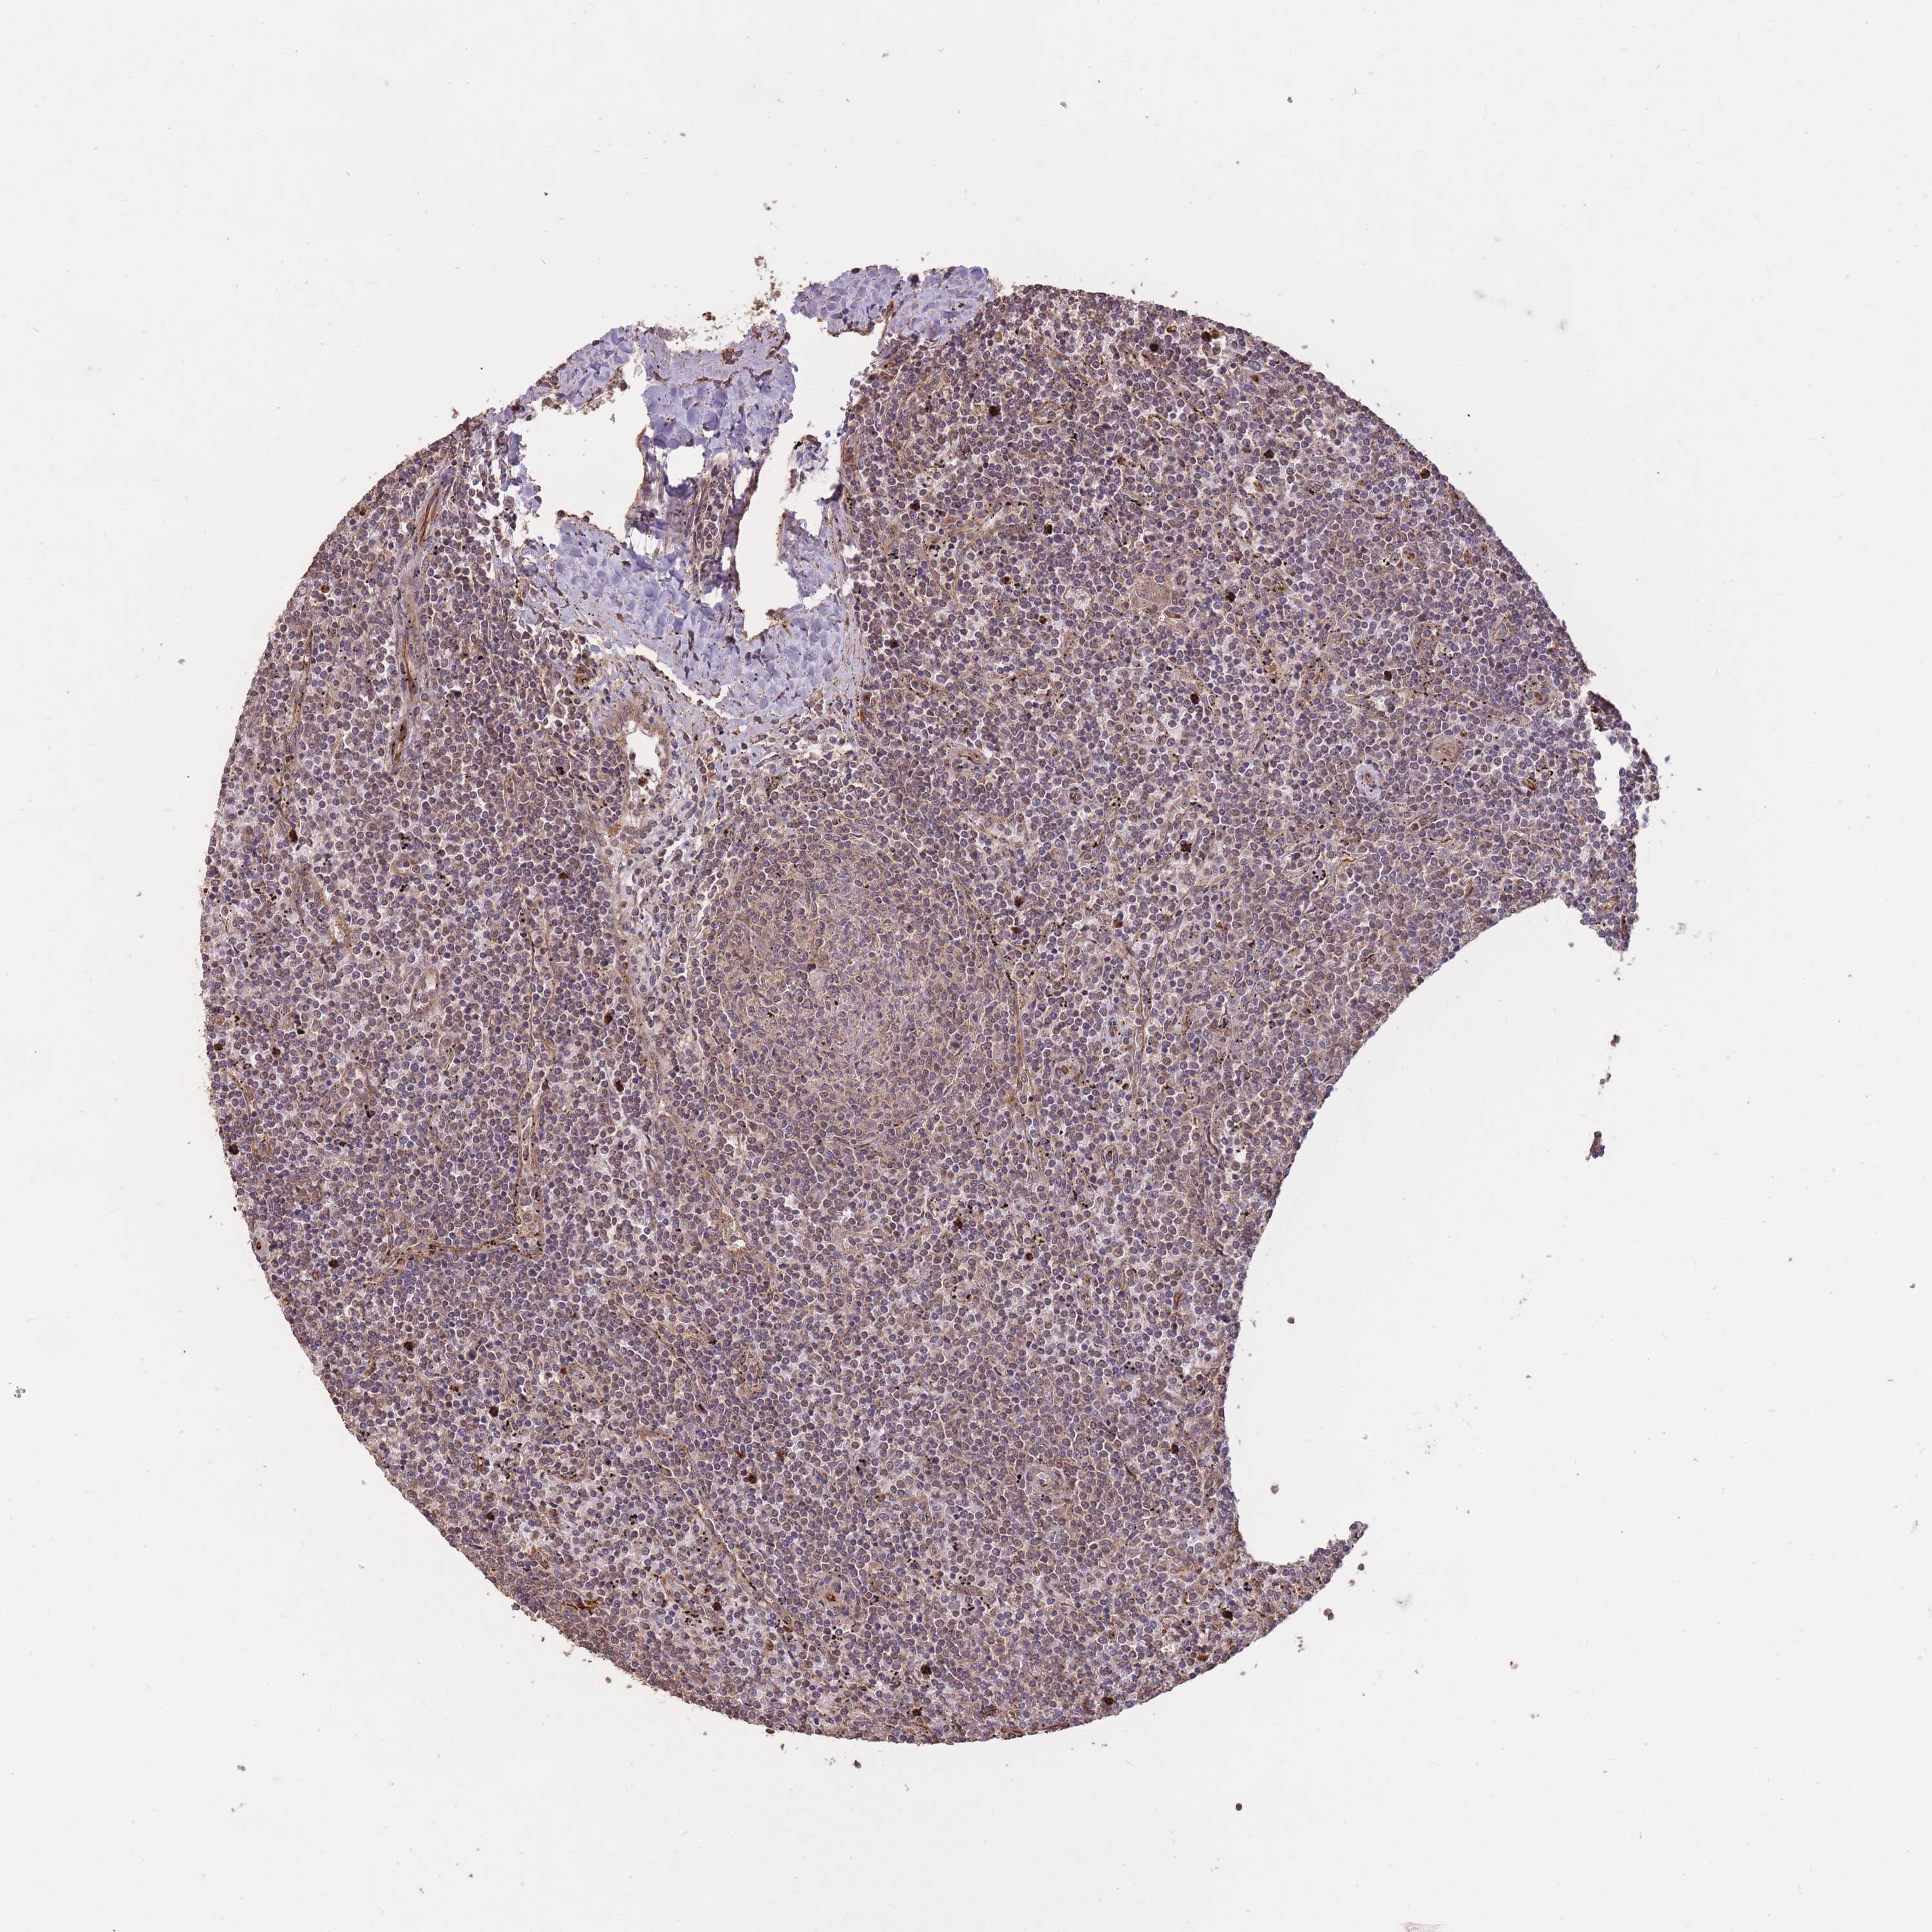

CANCER LYMPHOMA Show tissue menu

LYMPHOMA - Protein expressioni

A mouse-over function shows sample information and annotation data. Click on an image to view it in a full screen mode. Samples can be filtered based on level of antibody staining by selecting one or several of the following categories: high, medium, low and not detected. The assay and annotation is described here.

Each image is clickable and will lead to virtual microscopy that enables deeper exploration of all samples and also displays staining intensity scores, fraction scores and subcellular localization as well as patient and tissue information for each sample.

Antibody HPA045396

Antibody HPA070524

Antibody CAB025331

Staining

High

Medium

Low

Not detected

Intensity

Strong

Moderate

Weak

Negative

Quantity

>75%

75%-25%

<25%

None

Location

Nuclear

Cytoplasmic/membranous

Cytoplasmic/membranous,nuclear

Hodgkin's disease, NOS

Malignant lymphoma, non-Hodgkin's type, High grade

Malignant lymphoma, non-Hodgkin's type, Low grade